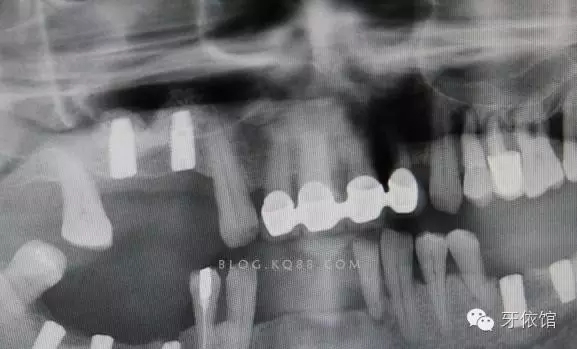

再用CAS鉆鉆透另一個(gè)窩洞的竇底,此時(shí)如果兩個(gè)窩洞離得近,那么第二個(gè)窩洞竇膜通過提升第一個(gè)窩洞竇膜時(shí)就已經(jīng)被提起了(不絕對(duì),這個(gè)病例就沒有被提起來,通過最后的X光片可以看到)。

植體的平行度很好

深度也很滿意。

術(shù)后X光片